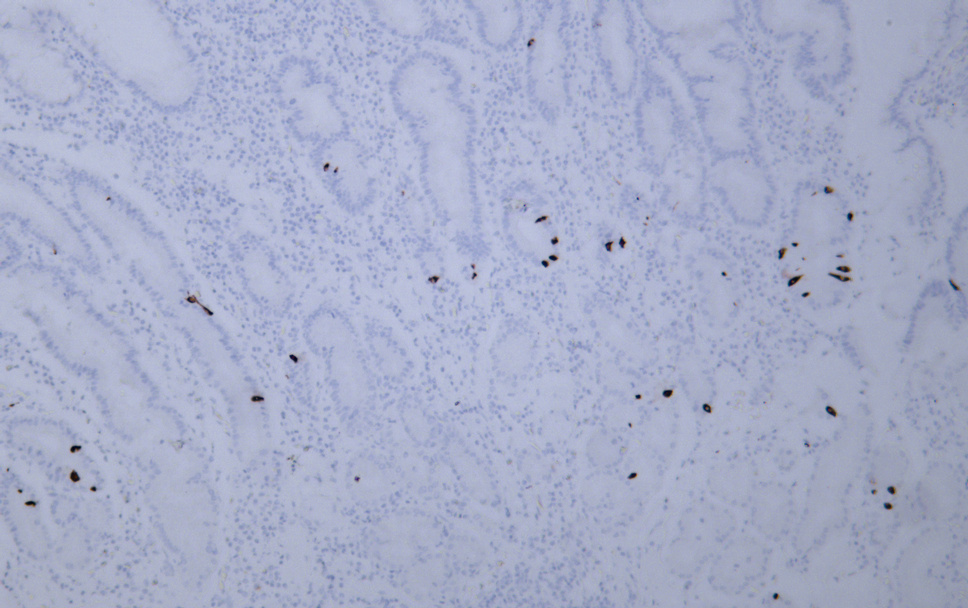

Total Gastrin Cell-Based Colorimetric ELISA Kit

ELISA

Colorimetric

function:Gastrin stimulates the stomach mucosa to produce and secrete hydrochloric acid and the pancreas to secrete its digestive enzymes. It also stimulates smooth muscle contraction and increases blood circulation and water secretion in the stomach and intestine.,online information:Gastrin entry,PTM:Sulfation enhances proteolytic processing, and blocks peptide degradation. Levels of sulfation differ between proteolytically-cleaved gastrins. Thus, gastrin-6 is almost 73% sulfated, whereas the larger gastrins are less than 50% sulfated. Sulfation levels are also tissue-specific.,PTM:Two different processing pathways probably exist in antral G-cells. In the dominant pathway progastrin is cleaved at three sites resulting in two major bioactive gastrins, gastrin-34 and gastrin-17. In the putative alternative pathway, progastrin may be processed only at the most C-terminal dibasic site resulting in the synthesis of gastrin-71.,similarity:Belongs to the gastrin/cholecystokinin family.,